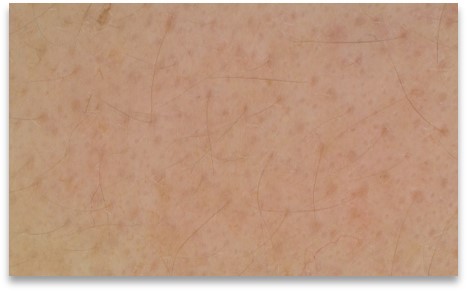

Roughness evaluation

The C-Cube is undeniably the best option for evaluating even the most subtle changes. Beyond measuring pimple elevation, it is able to observe very small signs of acne before they worsen with inflammation. This is equivalent to measuring the texture of the skin, invisible to the naked eye.

This can provide information about future cysts that may become inflamed in the following days.